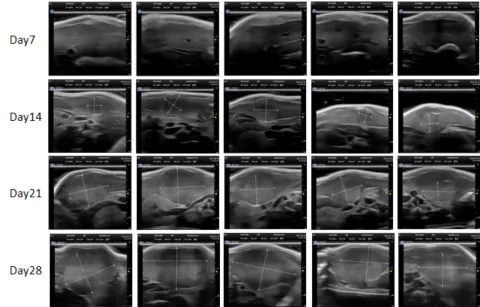

PDX Model (Growth Curve)